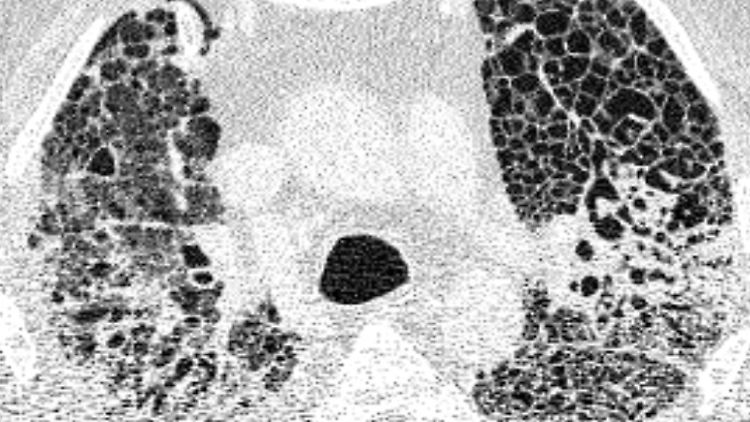

Computertomographie-Aufnahme (CT-Bild) der Lunge eines Patienten mit COVID-19-Lungenversagen. Helle Bereiche zeigen Verdichtungen und Vernarbungen des Lungengewebes.

(Foto: picture alliance/dpa/Charité)